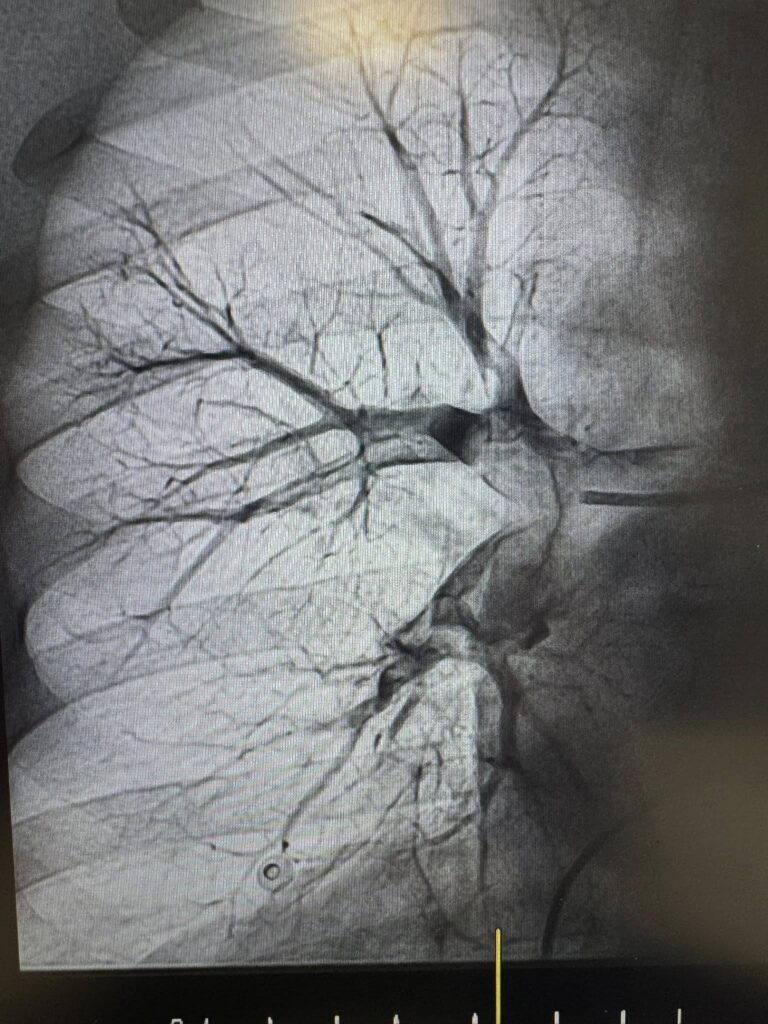

Команда лікарів Першого територіального медичного об’єднання міста Львова прийняла рішення в обох випадках провести ендоваскулярну тромбаспірацію — сучасне, малоінвазивне втручання, що дозволяє механічно видалити тромб із легеневої артерії без відкритої операції. Саме цю методику освоїли нещодавно на конгресі інтервенційних радіологів в Барселоні!

Під рентгенконтролем через судини катетером ми дісталися тромбів й видалили їх спеціальною системою аспірації.